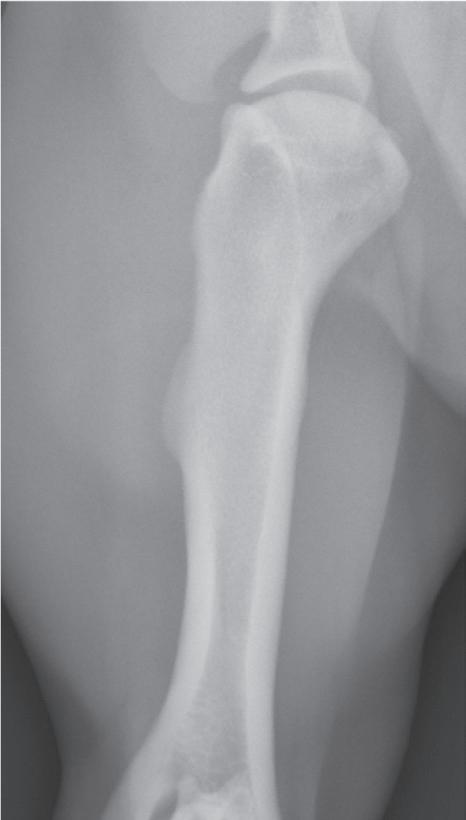

Lateral View

A lateral view is the orthogonal view to the dorsoplantar view and is made when the x-ray beam strikes the lateral or medial surface of a limb with the cassette or imaging plate on the opposite side (Figure 1-9). Although these views are called lateral views, lateral-medial or mediallateral is more correct depending on which side of the limb is struck by the primary x-ray beam.

In a medial-lateral view of a tarsus/pes, for example, the x-ray beam strikes the medial surface, and the image plate is on the lateral side (see Figure 1-10). In this view, the dorsal and palmar edges are projected in an unobstructed manner (see Figures 1-9 and 1-10). This does not

mean that only the lateral and medial edges can be evaluated because the infrastructure can still be assessed, but the dorsal and plantar edges are the only places where a surface change, such as a periosteal reaction or cortical erosion, will be able to be identifed.